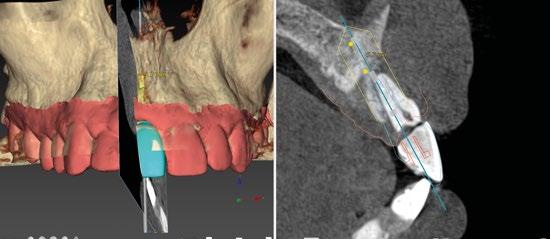

La digitalización es una realidad hoy en día en nuestra profesión, por lo tanto, es imprescindible que el odontólogo sepa sacar el máximo partido de todas las tecnologías disponibles con el fin de realizar tratamientos mucho más efectivos y predecibles. Las soluciones digitales en implantología cubren todas las etapas del tratamiento desde el diagnóstico, la planificación hasta la prótesis definitiva. Todos sabemos que el aspecto más crítico a la hora de realizar un tratamiento implantológico y de obtener un buen resultado es sin duda la posición 3D de nuestro implante.

Para ello es imprescindible tener bajo control todas aquellas variables que pueden influir en dicha posición tal como la proximidad a dientes vecinos, margen de la futura restauración, volumen de hueso existente, emergencia protética, profundidad del implante, aditamentos protéticos… Un sinfín de factores a tener en cuenta en

los cuales las herramientas digitales van a jugar un papel crucial al permitir, controlar todos esos aspectos antes de abordar el caso, pudiendo verificarlos y cambiarlos, incluso antes de afrontar la cirugía.

Por otro lado, es imprescindible y fundamental realizar un CBCT de la arcada a tratar para poder visualizar los tejidos duros y hacer una primera valoración del lecho implantario y de la patología existente. (Figura 4)

Otra prueba imprescindible hoy en día para nosotros es la realización de un escaneado intraoral que nos aporte la información de los tejidos superficiales y fusionado con el CBCT nos permita valorar los tejidos blandos del paciente. (Figura 5)

Para manejar todos estos datos vamos a necesitar de un software de diagnóstico y planificación digital como es el de DTX

StudioTM Implant en el cual vamos a abrir tanto el CBCT como el escaneado intraoral y nos va a permitir fusionar ambas mayas utilizando la herramienta SMARTFUSION. En un caso como éste, donde tenemos un incisivo central, superior, derecho, fracturado que vamos a extraer debemos realizar previamente la extracción Virtual

en el modelo digital para poder incorporarlo a la planificación de nuestro software. (Figuras 6 y 7)

Con todos estos datos fusionados en el DTX StudioTM Implant, lo que vamos a hacer es utilizar la función SMARTSETUP para tener un encerado Virtual que nos permita determinar la posición de la futura restauración del paciente, en función de la cual colocaremos nuestro implante y el aditamento más adecuado. (Figura 8)

En este caso, podemos ver que tenemos un defecto óseo vestibular, se trata de un defecto de una sola pared de la zona a implantar.

Intentamos planificar un implante inmediato y observamos la posibilidad de tener un buen anclaje apical por lo tanto nuestra primera opción va a ser la realización de un implante post extracción con regeneración de la pared vestibular mediate xenoinjerto óseo e injerto de tejido conectivo para mejorar el biotipo. (Figura 9)

En el caso de obtener suficiente torque, podríamos incluso valorar la opción de cargar dicho implante. En este caso lo que hacemos es planificar también un pilar con el fin de trabajar nuestra prótesis a nivel gingival, siguiendo la filosofía de “One Abutment-One Time (OAOT)”.

Lo realmente extraordinario de este software de diagnóstico y planificación es que en una sola imagen tenemos total control de la posición de nuestro implante y de nuestro pilar, en función del hueso de la encía y de la futura restauración. Por lo tanto vamos a realizar una implantología protética, y biológicamente guiada. (Figura 10)

Planificación

Una vez tenemos todos los datos, decidimos como primera opción realizar una cirugía guiada post extracción con regeneración y carga inmediata.

Otra de las ventajas que nos ofrece el software de diagnóstico y planificación DTX

StudioTM Implant es la posibilidad de diseñar una férula quirúrgica y exportarla con el fin de poder imprimirla de manera local y acortar así los tiempos de preparación. (Figuras 11 y 12)